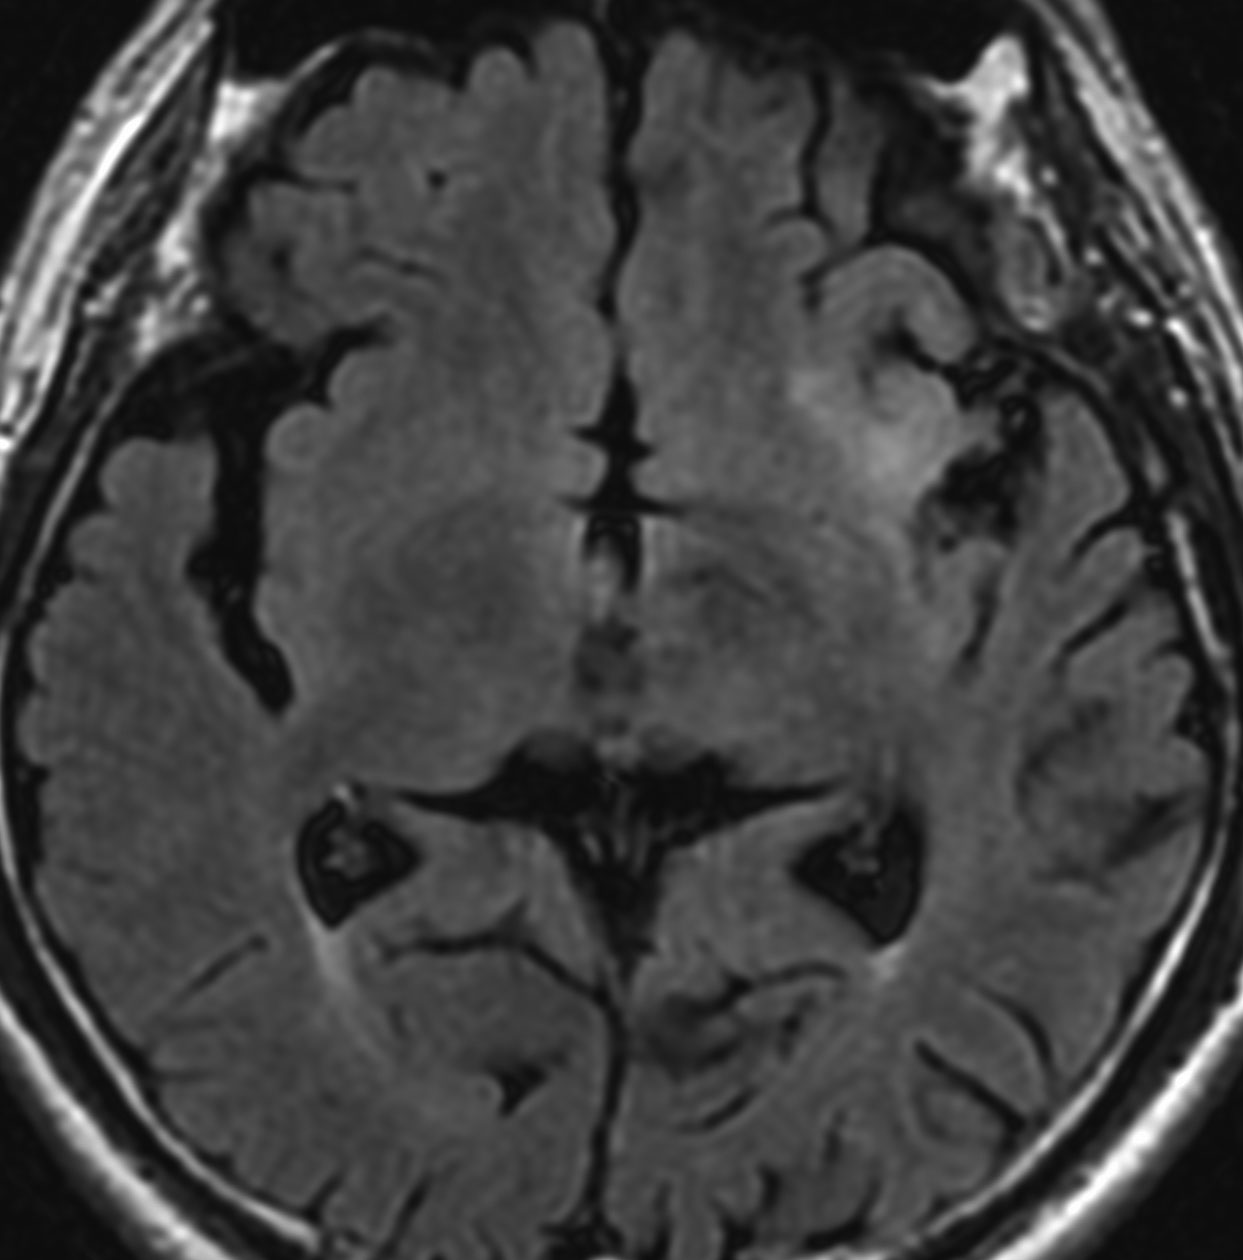

• MRI-T1強調画像では低信号となり,T2強調画像とフレア画像では高信号域となります

• グリオーマの中では,T2強調画像での腫瘍内部のコントラストが強く,石灰化の部分は強い低信号域として,のう胞は均一な強い高信号域となります

• 周囲脳組織浮腫あるいは腫瘍浸潤部は淡い高信号域として描出されます

• 脳浮腫を伴うものはグレード3の可能性が高いです

• ガドリニウムによる造影では,悪性度が高くなるにつれて部分的な増強像が増えます

MRI画像ではびまん性星細胞腫と区別がつかないものがあります

左は脳ドックで発見された時のMRIです。壮年男性で無症状でしたので経過観察をしました。fronto-insulo-temporal gliomaと呼ばれる腫瘍で,びまん性星細胞腫と区別がつきません。右は無治療で6年後の画像です。ごくわずかに増大していますが,患者さんは相変わらず無症状で普通に働いています。このように数年間経過を見ても問題ない例もありますし,逆に数ヶ月で顕著な増大傾向を示すものもあります。発見されたらまずは,MRIを2ヶ月くらいで繰り返してどのくらいの速さで進行するかどうかをみるのが大切です。